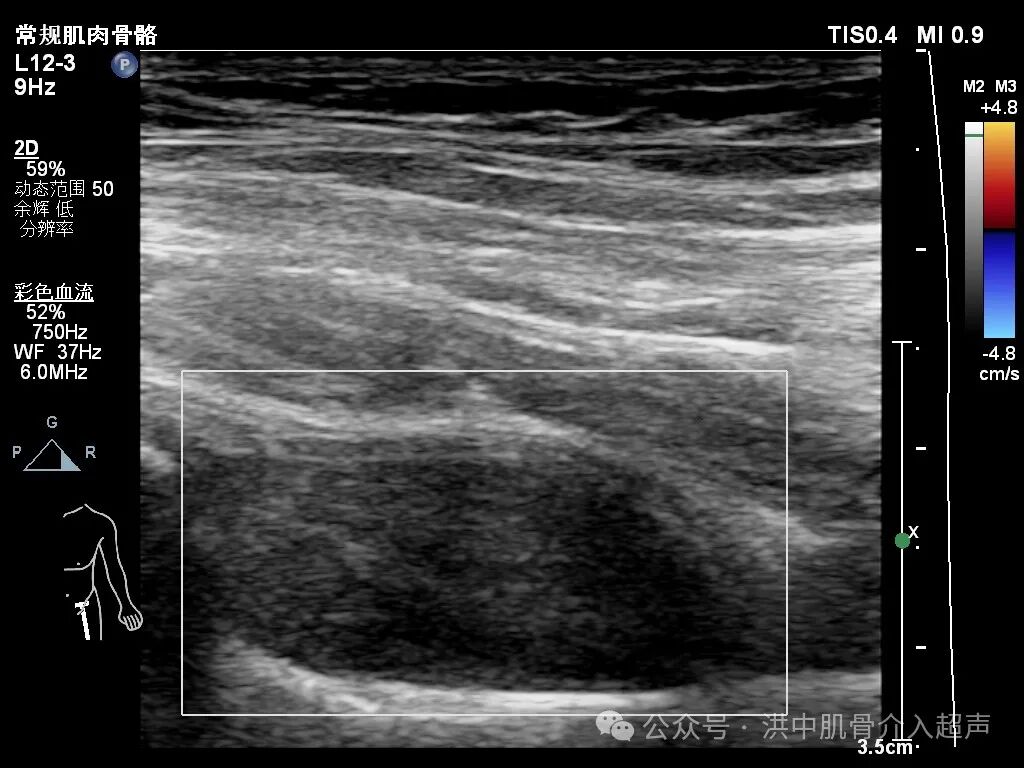

病例:23岁女性患者,左侧髋关节疼痛不适一月余,行走困难就诊。既往有过髋关节滑膜炎及治疗病史。

超声显示:股骨颈前间隙滑膜增生并少许积液。CDFI:少许点状血流信号。

结合临床症状及超声表现,考虑髋关节滑膜炎并积液。经与患者沟通同意后行超声引导下抽吸、注射治疗。

后期回访患者改善好转。